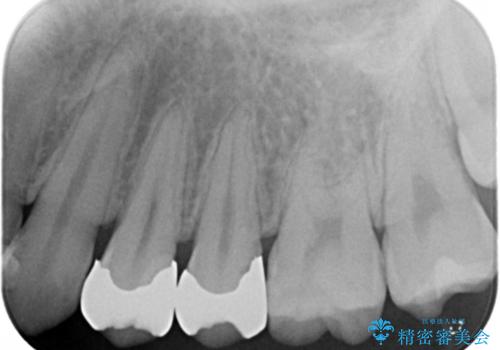

銀の詰め物を除去した後、う蝕が残っていないかを拡大鏡下で確認し

メタルインレーをそのままにしておくと、歯と詰め物の隙間から細菌が入り込み

虫歯の再発リスクが高まります。

セラミックの詰め物(e-maxインレー)は、歯と詰め物の隙間がなく

虫歯の再発リスクを下げる事ができます。